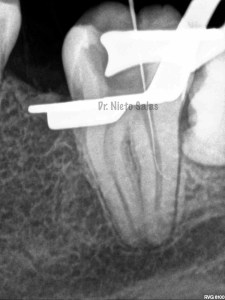

La otra pieza, el 3.7, se instrumentó con sistema Protaper y obturación con Ola continua de Calor y un back-filling con la pistola Obtura II.

(buscamos siempre algún conducto lateral, para intentar asegurarnos de su limpieza)

Y una en las demás proyecciones MESIO Y DISTO: